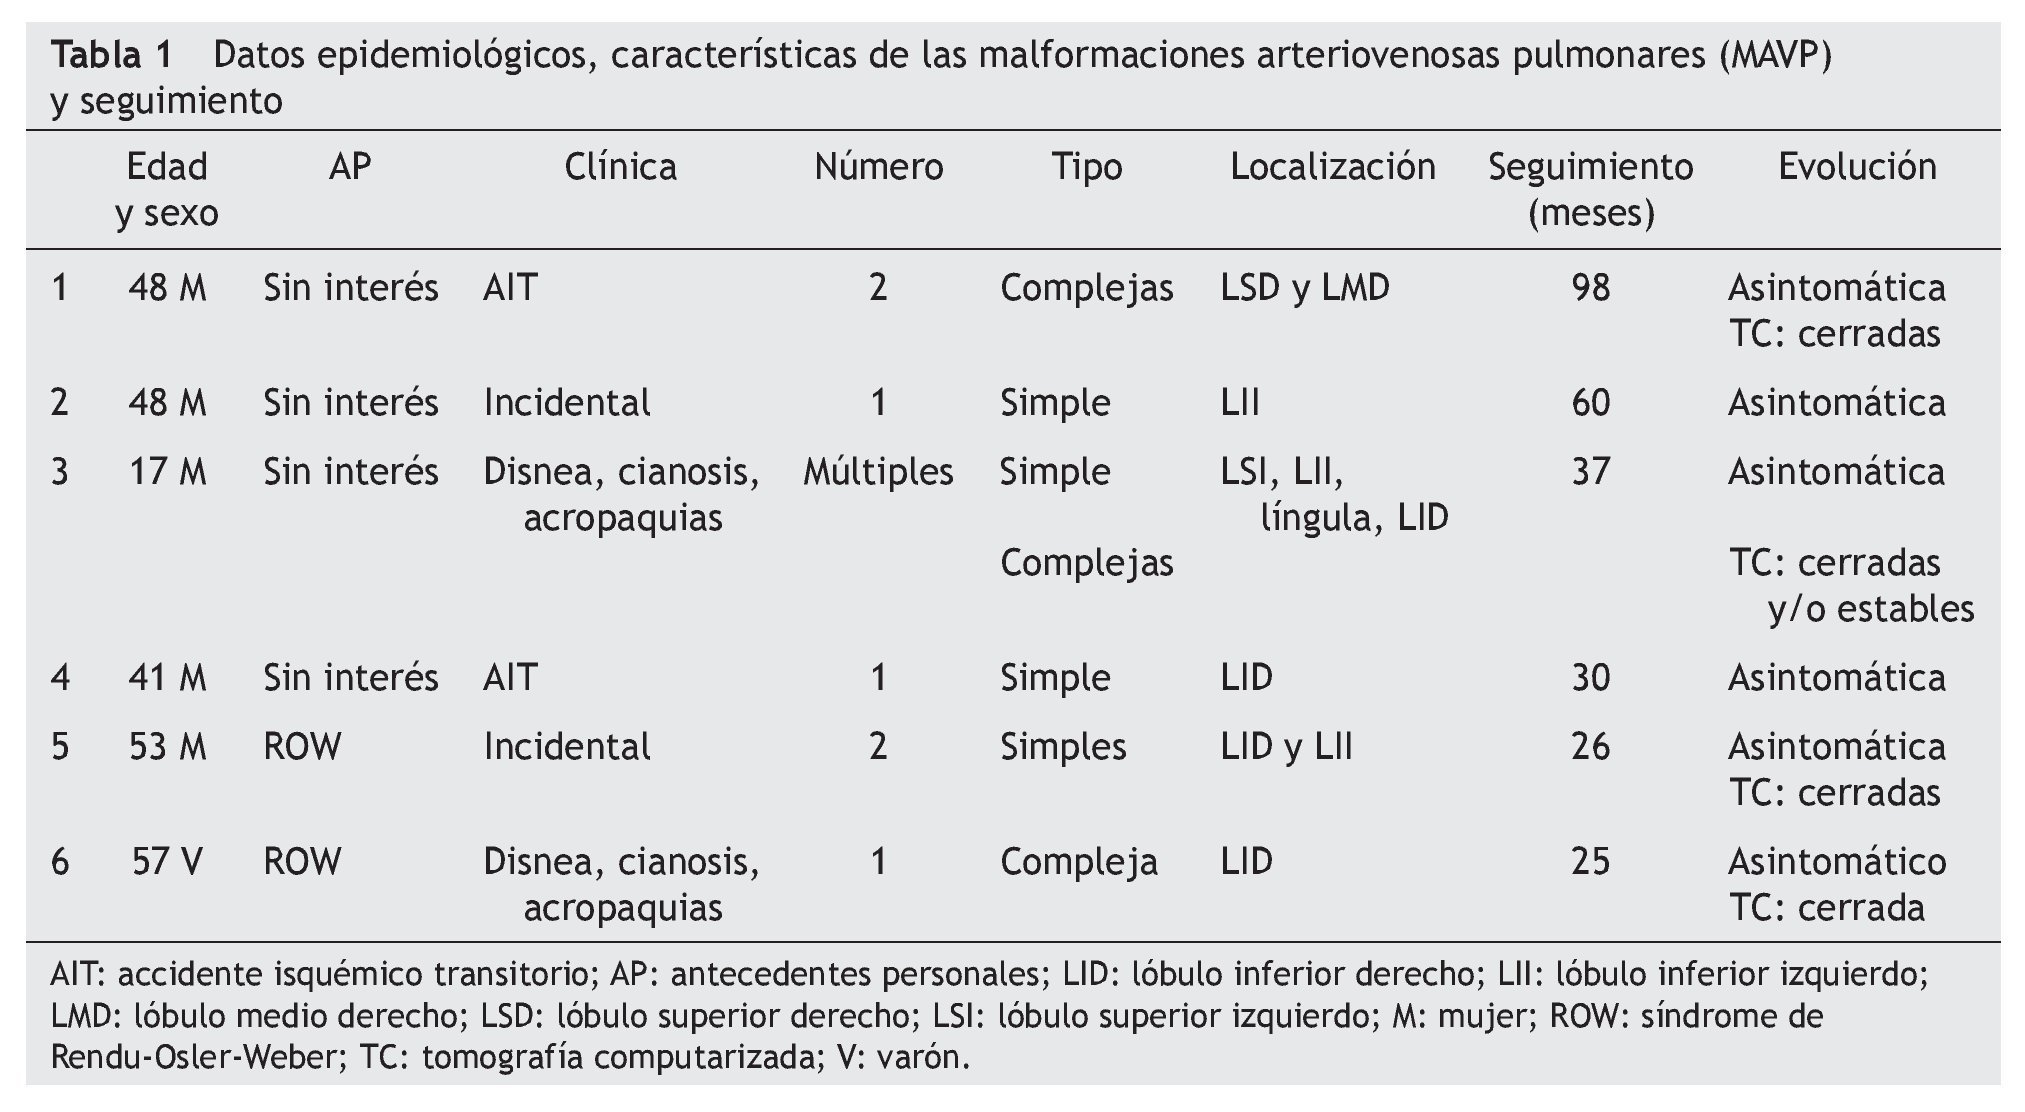

Desde diciembre de 1997 a febrero de 2004, un total de 6 pacientes con MAVP se trataron endovascularmente mediante embolización con "espirales metálicas" ocoils en el Hospital Reina Sofía de Córdoba. Los pacientes (5 mujeres y 1 varón) tenían una edad media de 44 años (rango, 16-57) y 2 de ellos presentaban síndrome de ROW. Clínicamente, en dos casos la/s MAVP/s debutaron con cuadros de accidente isquémico transitorio (AIT), 2 presentaban insuficiencia respiratoria, cianosis y acropaquias, y en 2 la MAVP fue un hallazgo incidental en la radiografía de tórax. Mediante radiografía, tomografía computarizada (TC) y/o angiografía, se llegó al diagnóstico de MAVP múltiples en 1 paciente, dobles en 2 y únicas en 3.

En la tabla 1 se recogen datos epidemiológicos de los pacientes, características de las MAVP y hallazgos clinicorradiológicos del seguimiento.